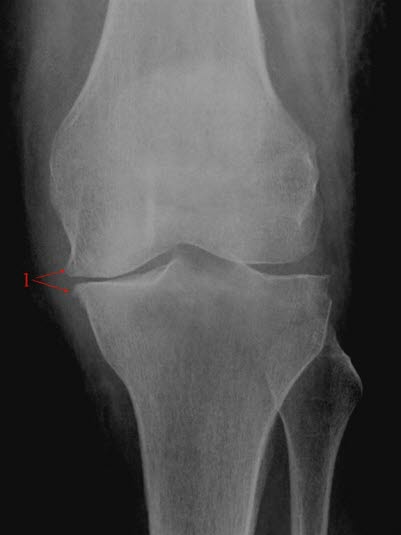

Gonartrose, moderat, front

Moderat artrose medialt i kneleddet. Redusert bruskhøyde og små påleiringer rundt leddflatene (1)